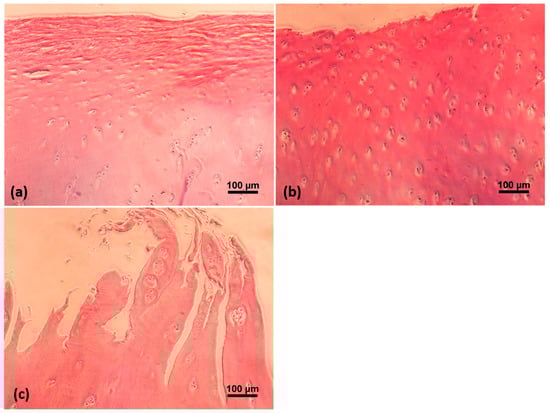

4.4. Histological Assessment

- Pritzker, K.P.; Gay, S.; Jimenez, S.A.; Ostergaard, K.; Pelletier, J.P.; Revell, P.A.; Salter, D.; van den Berg, W.B. Osteoarthritis cartilage histopathology: Grading and staging. Osteoarthr. Cartil. 2006, 14, 13–29. [Google Scholar] [CrossRef] [PubMed]